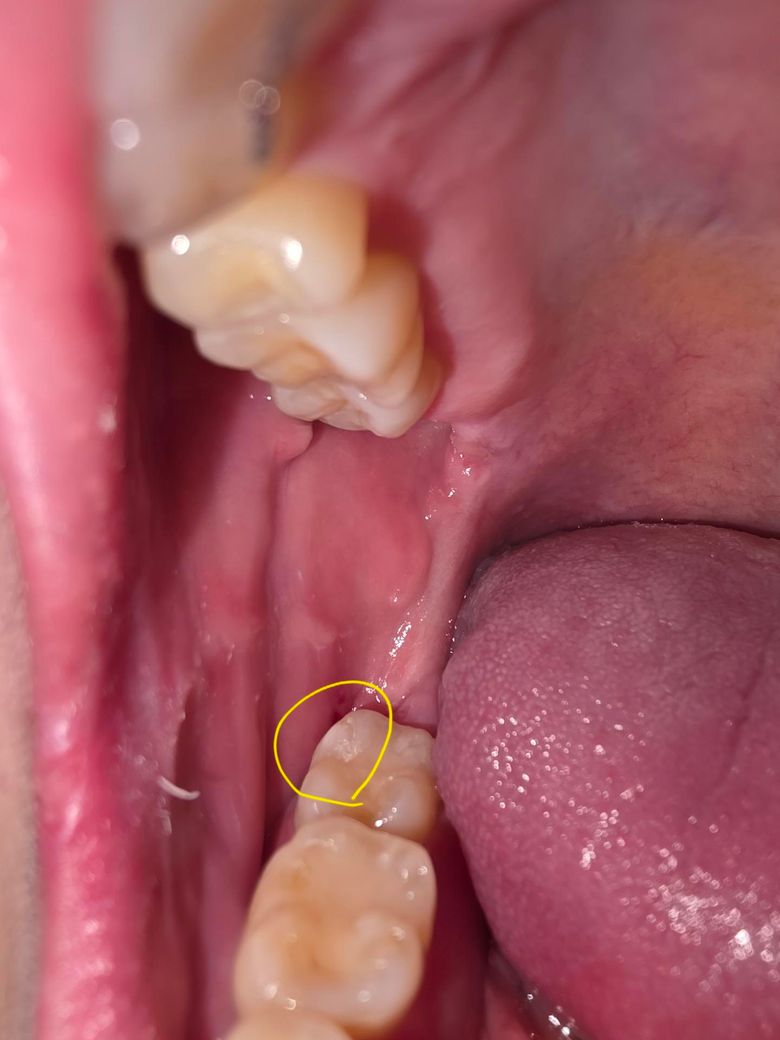

레진한 부분에 생긴 스크레치난 부분 치과가서 연마 해야될까요? ㅠㅠ

이러면 안돼는거 알지만... 충치인지 바늘가지고 치아 긁어보다가 레진쪽을 긁었는데요.. 중간 사진 처럼 긁혀있다가 양치하고 나니 마지막 사진 처럼 스크레치가 남아있는데 양치로는 스크레치 없어지지 않을까요? 지피티나 제미나이에게 물어보니 2차우식이나 착색 때문에 연마하는게 좋다고 그래서요... ㅠㅠ 치과가서 연마가 필요한지 궁금합니다.

• 2번 째 사진